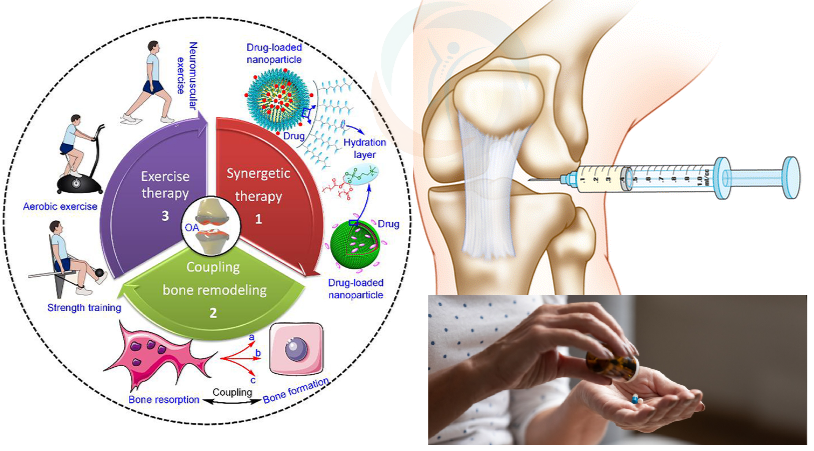

درمان غیرجراحی آرتروز

چالش های بهترین درمان آرتروز شامل موارد متعددی است که روند کنترل و بهبود بیماری را پیچیده میکند. یکی از مهمترین چالشها، ماهیت تدریجی و پیشرونده بیماری است که غضروف مفصل به مرور تحلیل میرود و ترمیم کامل آن ممکن نیست. به همین دلیل، درمانها بیشتر به سمت کنترل علائم و کاهش درد متمرکز میشوند تا توقف کامل بیماری.

علاوه بر این، تنوع علائم و شدت آن در بیماران مختلف، نیاز به برنامه درمانی شخصیسازی شده را ضروری میکند که ممکن است به زمان و منابع بیشتری نیاز داشته باشد. همچنین، برخی داروهای ضد التهاب و مسکنها ممکن است عوارض جانبی گوارشی یا کلیوی داشته باشند، بهخصوص در بیماران مسن که مصرف طولانیمدت این داروها میتواند مشکلات جدیدی ایجاد کند.

عوامل دیگری مانند چاقی، عدم تحرک کافی، و وجود بیماریهای زمینهای مثل دیابت یا مشکلات قلبی نیز روند بهترین درمان آرتروز را پیچیدهتر میکنند. محدودیت در دسترسی به روشهای نوین درمانی، هزینههای بالای برخی جراحیها یا تزریقات مفصلی و همچنین مقاومت بیمار در تغییر سبک زندگی از دیگر چالشهای مهم در مدیریت آرتروز هستند.

استفاده از داروهایی مانند استامینوفن به منظور کاهش درد و افزایش راحتی بیمار. این داروها به صورت خوراکی یا موضعی مصرف میشوند و معمولاً در دردهای خفیف تا متوسط مؤثرند.

شامل داروهایی مانند ایبوپروفن و ناپروکسن که برای کاهش التهاب و درد در مفاصل کاربرد دارند. این داروها به بهبود حرکت و کاهش تورم نیز کمک میکنند.

کورتون برای کنترل التهابهای شدید و کاهش درد بهکار میرود. این داروها معمولا مستقیم داخل مفصل تزریق می شوند. ژل ، پی آر پی و ازون نیر داخل مفاصل بخصوص زانو تزریق می شوند. تزریق داخل مفاصل از روشهای موثر بهترین درمان آرتروز هست.

ورزش درمانی اختصاصی برای تقویت عضلات اطراف مفصل، افزایش دامنه حرکتی، کاهش خشکی مفصل و بهبود انعطافپذیری بدن. ورزش درمانی اثر اثبات شده ای در بهترین درمان آرتروز دارد.